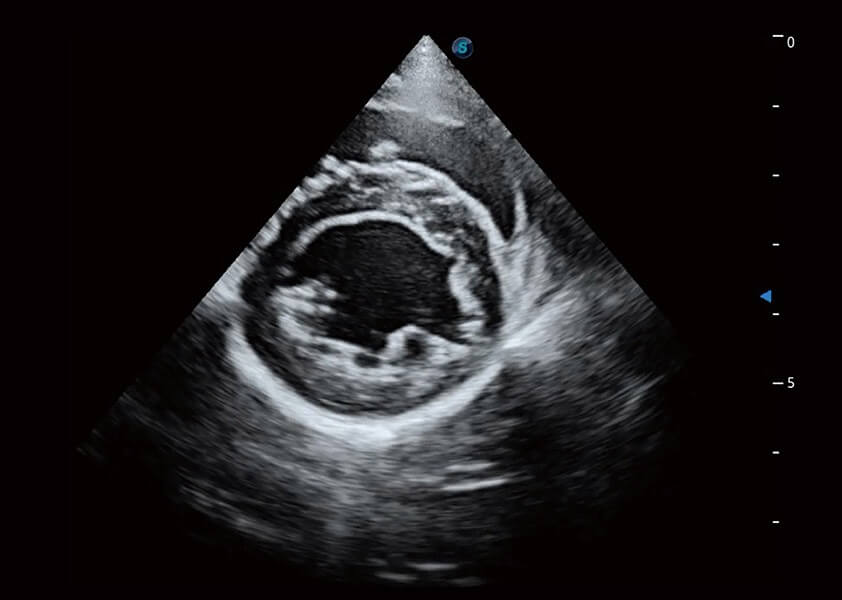

(犬)乳头肌短轴

(猫)二尖瓣M型